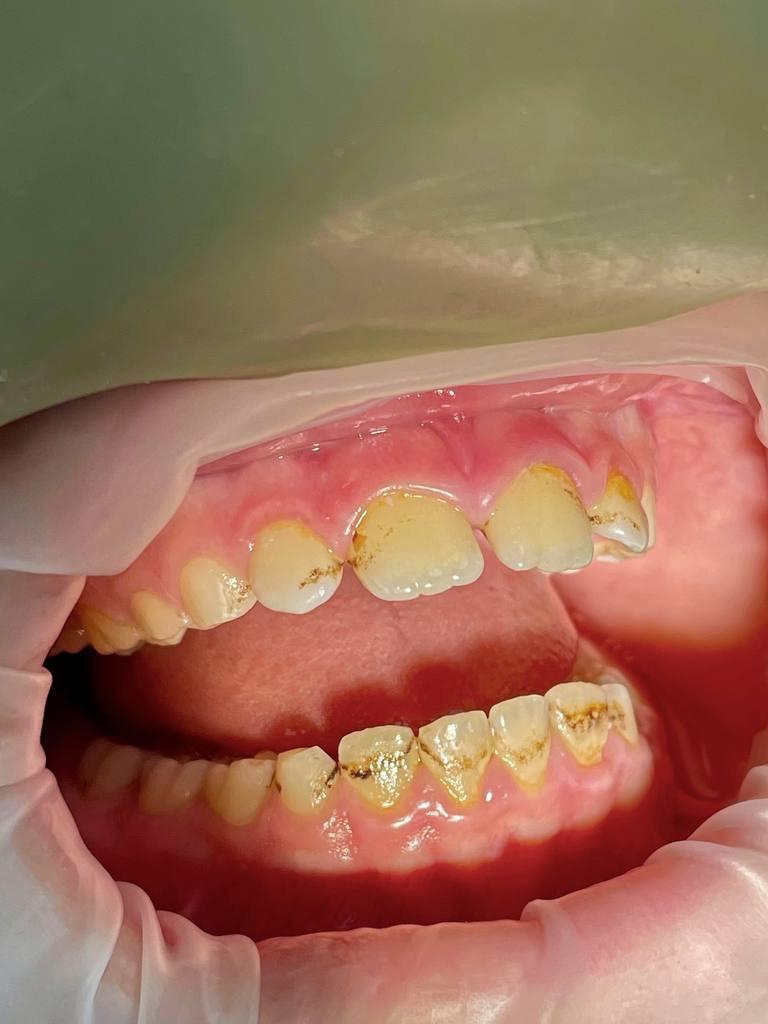

Пациент обратился с жалобами на зубные отложения: пигментированный зубной налет, мягкий зубной налет, наддесневой и поддесневой минерализованный зубной камень.

Удаление наддесневыз зубных отложений: пигментированный зубной надет, минерализованный зубной камень.

Пациент обратился с жалобами на зубные отложения: пигментированный зубной налет, мягкий зубной налет. Наддесневой и поддесневой минерализованный зубной камень.